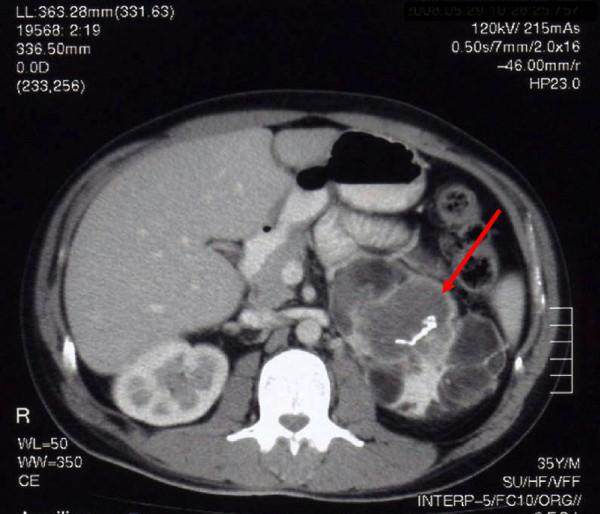

A 35-year-old Caucasian man was admitted to the emergency room with an Addisonian crisis. He had been diagnosed with congenital adrenal hyperplasia in the neonatal period. He acknowledged poor adherence to treatment and irregular medical assistance. Physical examination revealed marked cutaneous and gingival hyperpigmentation, hypotension, and hard nodules in the upper pole of both testicles. Blood analysis showed mild anemia and hyponatremia and no evidence of acute infection. Endocrine evaluation showed very low cortisol levels, low dehydroepiandrosterone-sulfate and elevated corticotropin, 11-deoxycortisol and delta-4-androstenedione. The concentration of 17-hydroxyprogesterone was 20,400ng/dL. After the cosyntropin stimulation test the pattern was similar and there was no significant increase in cortisol or 17-hydroxyprogesterone. The abdominal computed tomography scan revealed grossly enlarged and heterogeneous adrenal glands (left, 12cm; and right, six cm). A bilateral adrenalectomy was performed and pathologic examination revealed adrenal myelolipomas with nodular cortical hyperplasia. The sonogram showed bilateral heterogeneous masses on the upper pole of both testes which corresponded to the nodular hyperplasia of adrenal rest tissues. The genetic study revealed compound heterozigoty (mutations R124H and R356W), suggestive of a phenotypically moderate disease. We performed a cosyntropin stimulation test after adrenalectomy. The steroidogenic profile displayed the same unusual features, indicating an important contribution from the adrenogenital cells.

This case illustrates that congenital adrenal hyperplasia due to 21-hydroxylase deficiency can progress to severe acute and chronic complications. The masses in the patient's adrenal glands and testicles resulted from chronically elevated adrenocorticotropic hormone and growth of adrenocortical cells. The basal and stimulated steroid profile, before and after adrenalectomy, revealed an unexpected pattern, suggesting significant contribution of the testicular adrenal cells to the steroidogenesis.